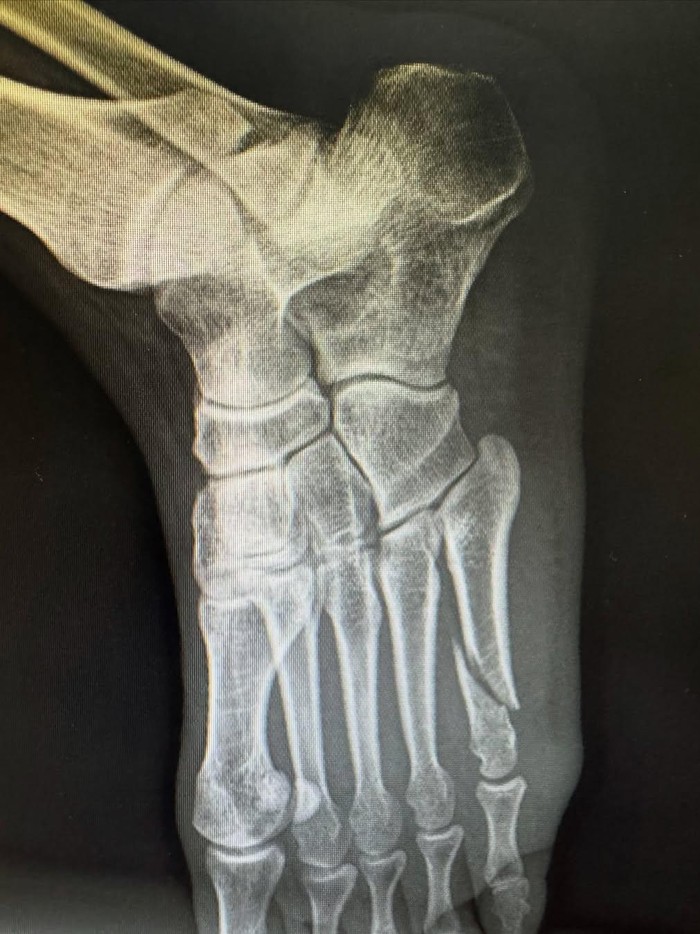

Ini hasil rontgen bagian kaki Irwansyah yang mengalami patah tulang. Foto: dok. Instagram Irwansyah